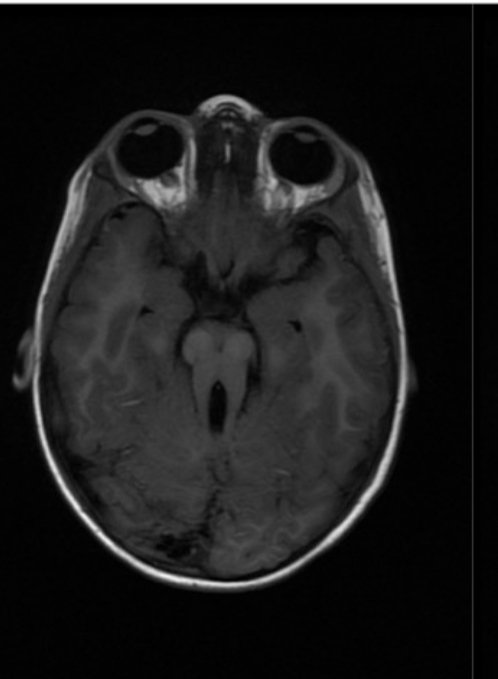

Molar Tooth sign in a patient with Joubert Syndrome Image

Molar tooth sign

appearance of the midbrain in an axial section in which the elongated superior cerebellar peduncles give the midbrain an appearance reminiscent of a molar or wisdom tooth.